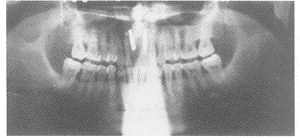

根尖下截骨,平均骨段下降4 mm(3~6 mm)微型钛板固定,同期行上颌前部种植术,下颌前部根尖下截除之骨块植入上颌前部种植区域唇侧,共植入种植体10颗。术后患者均得到正常咬合关系。术后7个月时行种植体上部结构修复,均为种植体烤瓷冠固定修复,因种植体位于理想的位置与轴向,种植修复的功能与美学效果理想(图2~4),术后平均追踪2年,无种植体脱落松动。

图4 上颌

种植修复完成(种植体烤瓷冠),咬合关系正常

图5 患者术后3个月X线片示,下颌

根尖下截骨线仍可见,上颌

区域种植体骨结合良好